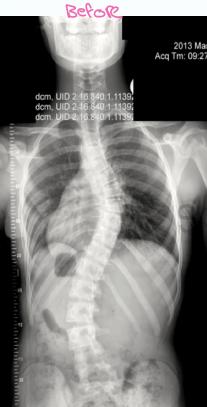

Imaging

- X-ray:

- AP and LAT of entire spine (Cobb angle measurement)

- AP pelvis (Risser grade)

Cobb Angle Measurement

- Select most tilted vertebrae above and below curve apex

- Angle between intersecting lines drawn perpendicular to superior vertebra top and inferior vertebra bottom